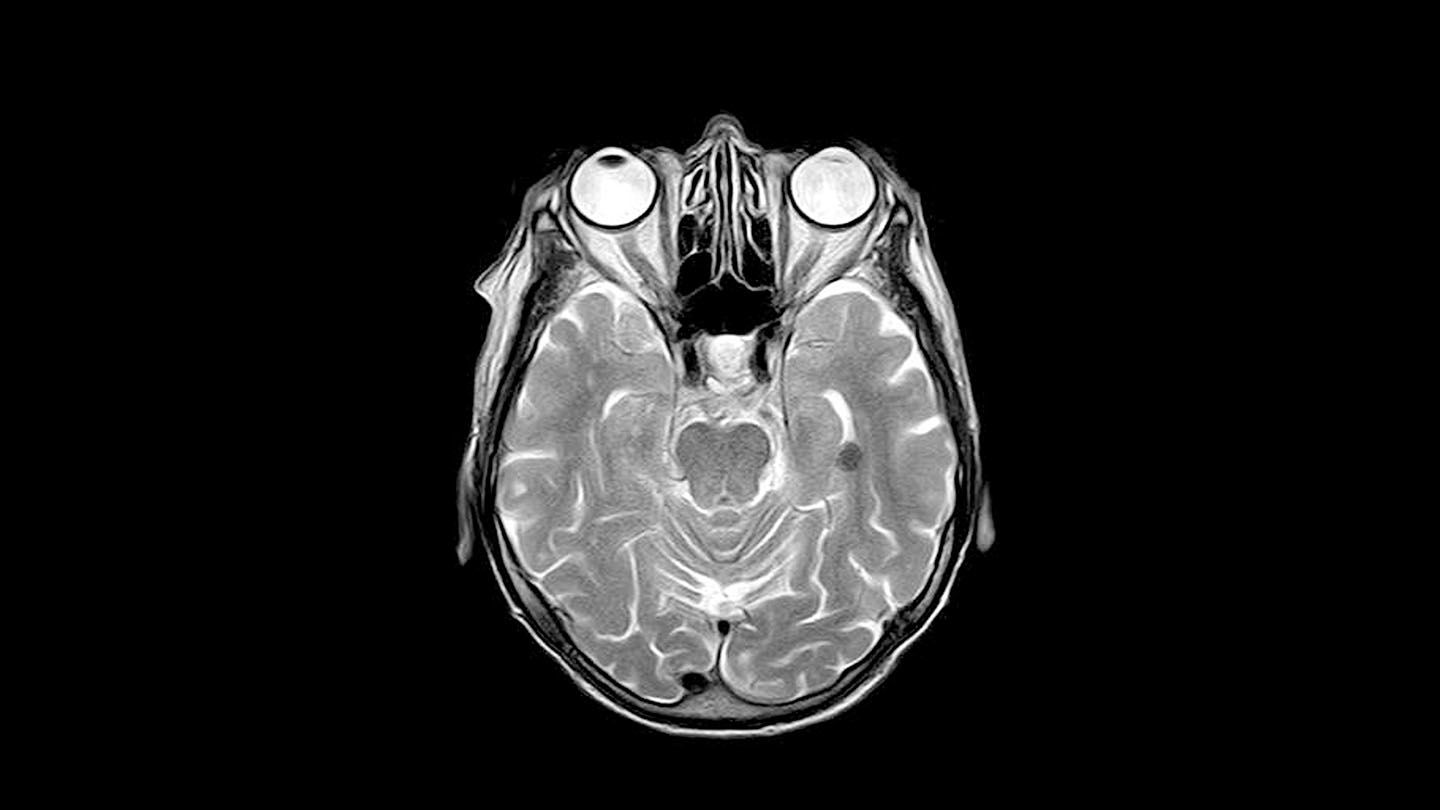

Ett viktigt verktyg för barncancervården är den så kallade MR-kameran, som bland annat används för att diagnosticera hjärntumörer. I dag behöver barn oftast...

Barncancerforskning: Forskare har fått ny kunskap om vad som händer med barns hjärnor när de strålas. Den kan leda fram till att man i framtiden bättre ska kunna skydda mot...

Forskningsreportage: Det är vanligt att barn som fått strålning mot tumörer i hjärnan får kognitiva problem senare i livet. Men nu har forskare med finansiering från Barncancerfonden...

Forskningsreportage: Strålning av barns hjärnor kan ofta orsaka många och svåra biverkningar som påverkar kroppen resten av livet. Nu har två göteborgsforskare fått anslag från...